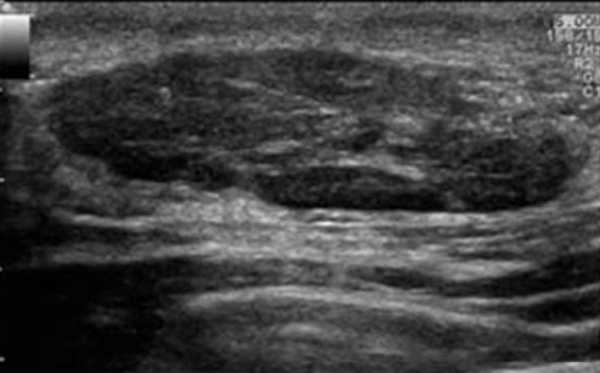

На снимке образование, подозрительное на фибросаркому. При допплерографии (справа) определяется кровоток в сосудах, питающих опухоль